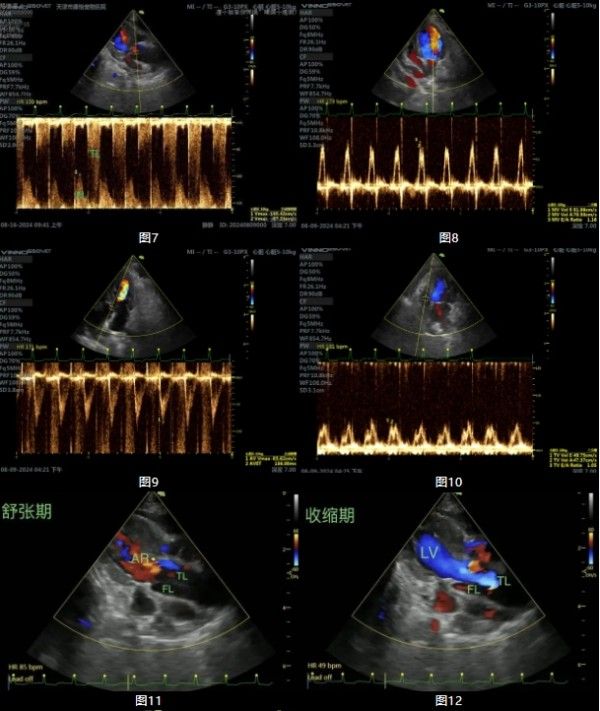

心脏各腔室未见明显扩张,室壁不厚,主观运动无异常,ECG节律齐,轻度心包积液。主动脉舒张期反流,升主动脉根部扩张,腔内纵切面可见隔膜样回声,呈线状或条索状随心动周期摆动,将管腔分为真假两腔(图11-图18)。彩色多普勒下管腔内可探及双向血流信号,收缩期真腔内明亮快速血流,假腔内暗淡慢速血流。收缩期血流由真腔流入假腔,假腔扩张,真腔被挤压。舒张期从假腔流入真腔,假腔内径轻度回缩。收缩功能及舒张功能未见明显异常。超声提示典型的升主动脉夹层影像,主动脉反流,心包积液。如图:

注:FL:假腔 TL:真腔,图7标记TL波形为收缩期真腔血流频谱,标记FL波形为假腔舒张期血流频谱。4.